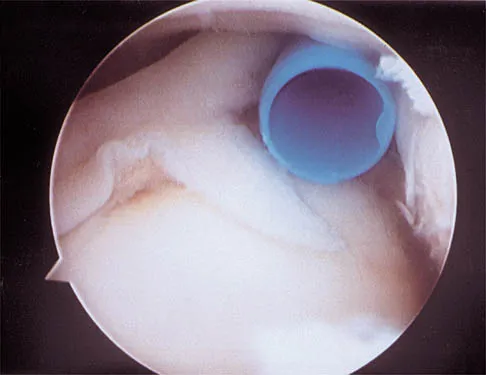

A 21-year-old collegiate pitcher has had pain in his dominant shoulder for the past 3 months despite management consisting of rest, rehabilitation, and an analysis of throwing mechanics. An arthroscopic photograph from the posterior portal is shown in Figure 10. The biceps anchor to the bone was not detached to probing. Treatment of the lesion to the left of the cannula should consist of arthroscopic